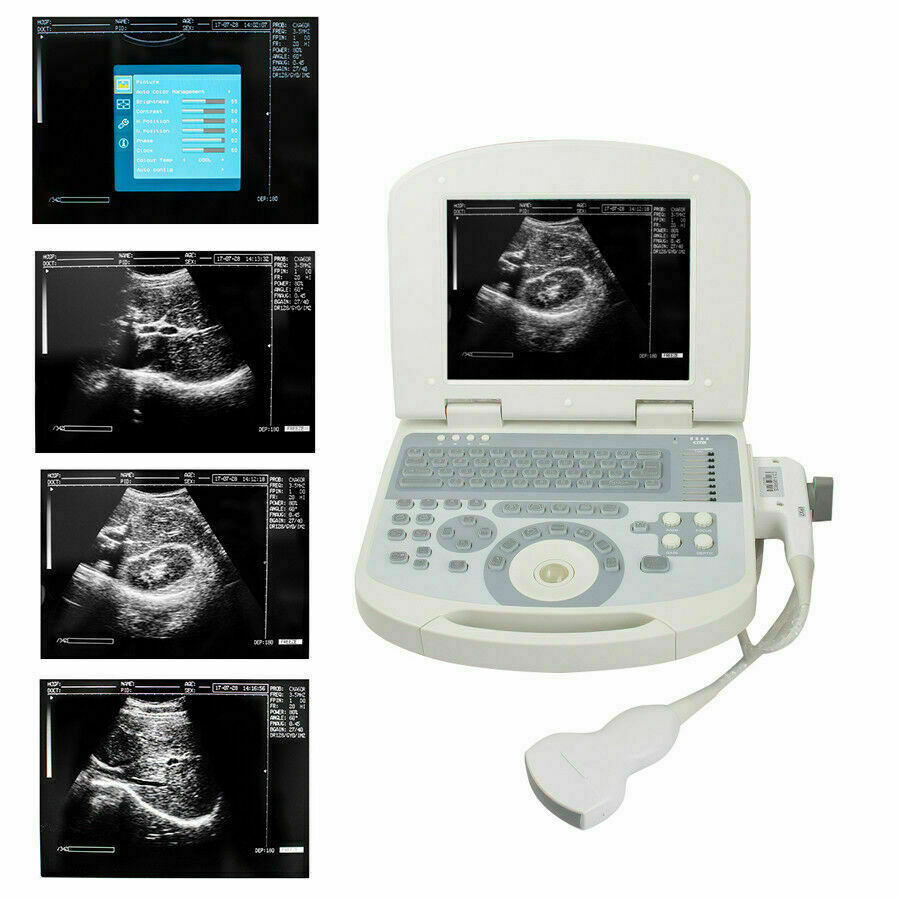

New Portable Laptop Machine Digital Ultrasound Scanner, 3.5 Micro Convex Probe

The new Portable Laptop Digital Ultrasound Scanner features a 3.5MHz micro convex probe for versatile imaging capabilities. This compact machine is designed for high-quality diagnostics in various medical settings, providing detailed ultrasound images. Its lightweight design and user-friendly interface make it ideal for healthcare professionals who require mobility and ease of use. The scanner is suitable for a range of applications, ensuring accurate assessments and improved patient care. Overall, it's a reliable solution for modern medical imaging needs.